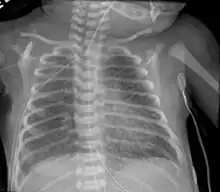

Chest radiography showing severe pulmonary interstitial emphysema

A chest X ray may show a "salt and pepper" appearance due to the linear lucencies that are present.